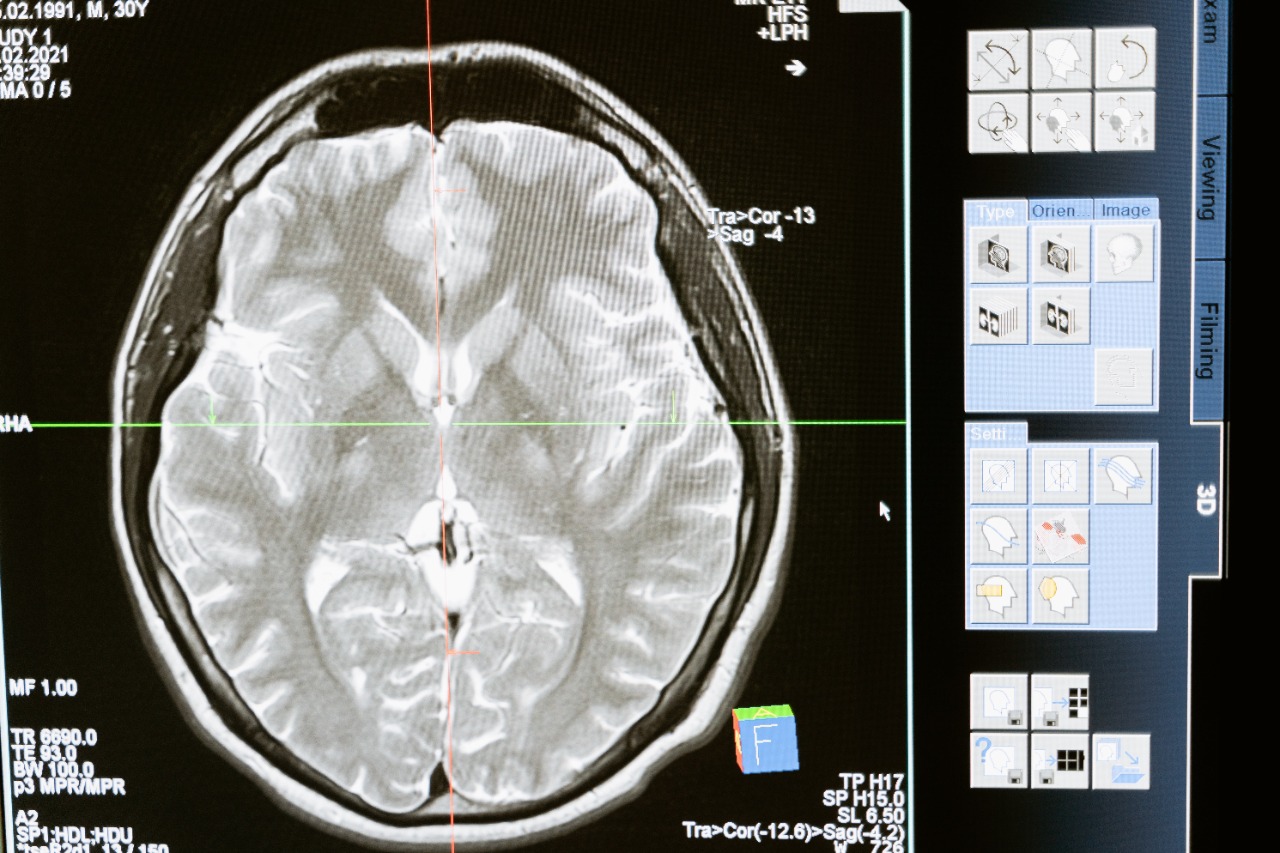

Para obtener el diagnóstico se realiza una evaluación multidisciplinaria integrada por neurología, neurocirugía, ortopedia y médico pediatra; además, se necesitan imágenes computarizadas y la resonancia magnética cerebral, esta última es la ideal.